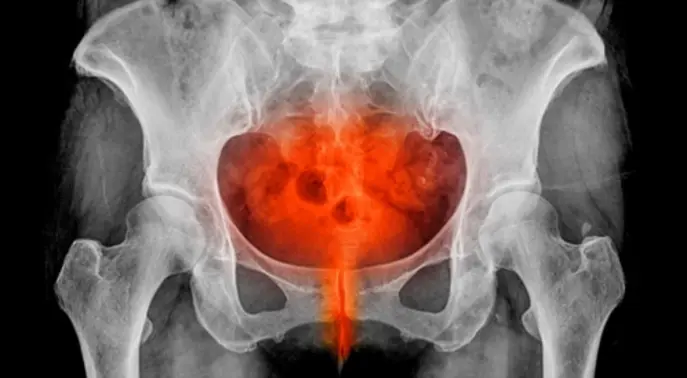

مرض التهاب الحوض (PID) هو حالة صحية خطيرة تصيب الأعضاء التناسلية للمرأة، ويمكن أن يمتد ليشمل الرحم، قنوات فالوب، والمبيضين. يتجاوز هذا المرض مجرد الشعور بألم في البطن، فهو ينذر بمضاعفات قد تكون وخيمة إذا تُرك دون علاج. فهم هذا المرض أمر بالغ الأهمية للحفاظ على صحة المرأة وخصوبتها.

مرض التهاب الحوض (PID) هو عدوى تصيب الأعضاء التناسلية الأنثوية في منطقة أسفل البطن. غالبًا ما يبدأ هذا الالتهاب في المهبل ثم ينتشر تدريجيًا ليصيب الرحم، عنق الرحم، قنوات فالوب، والمبيضين.